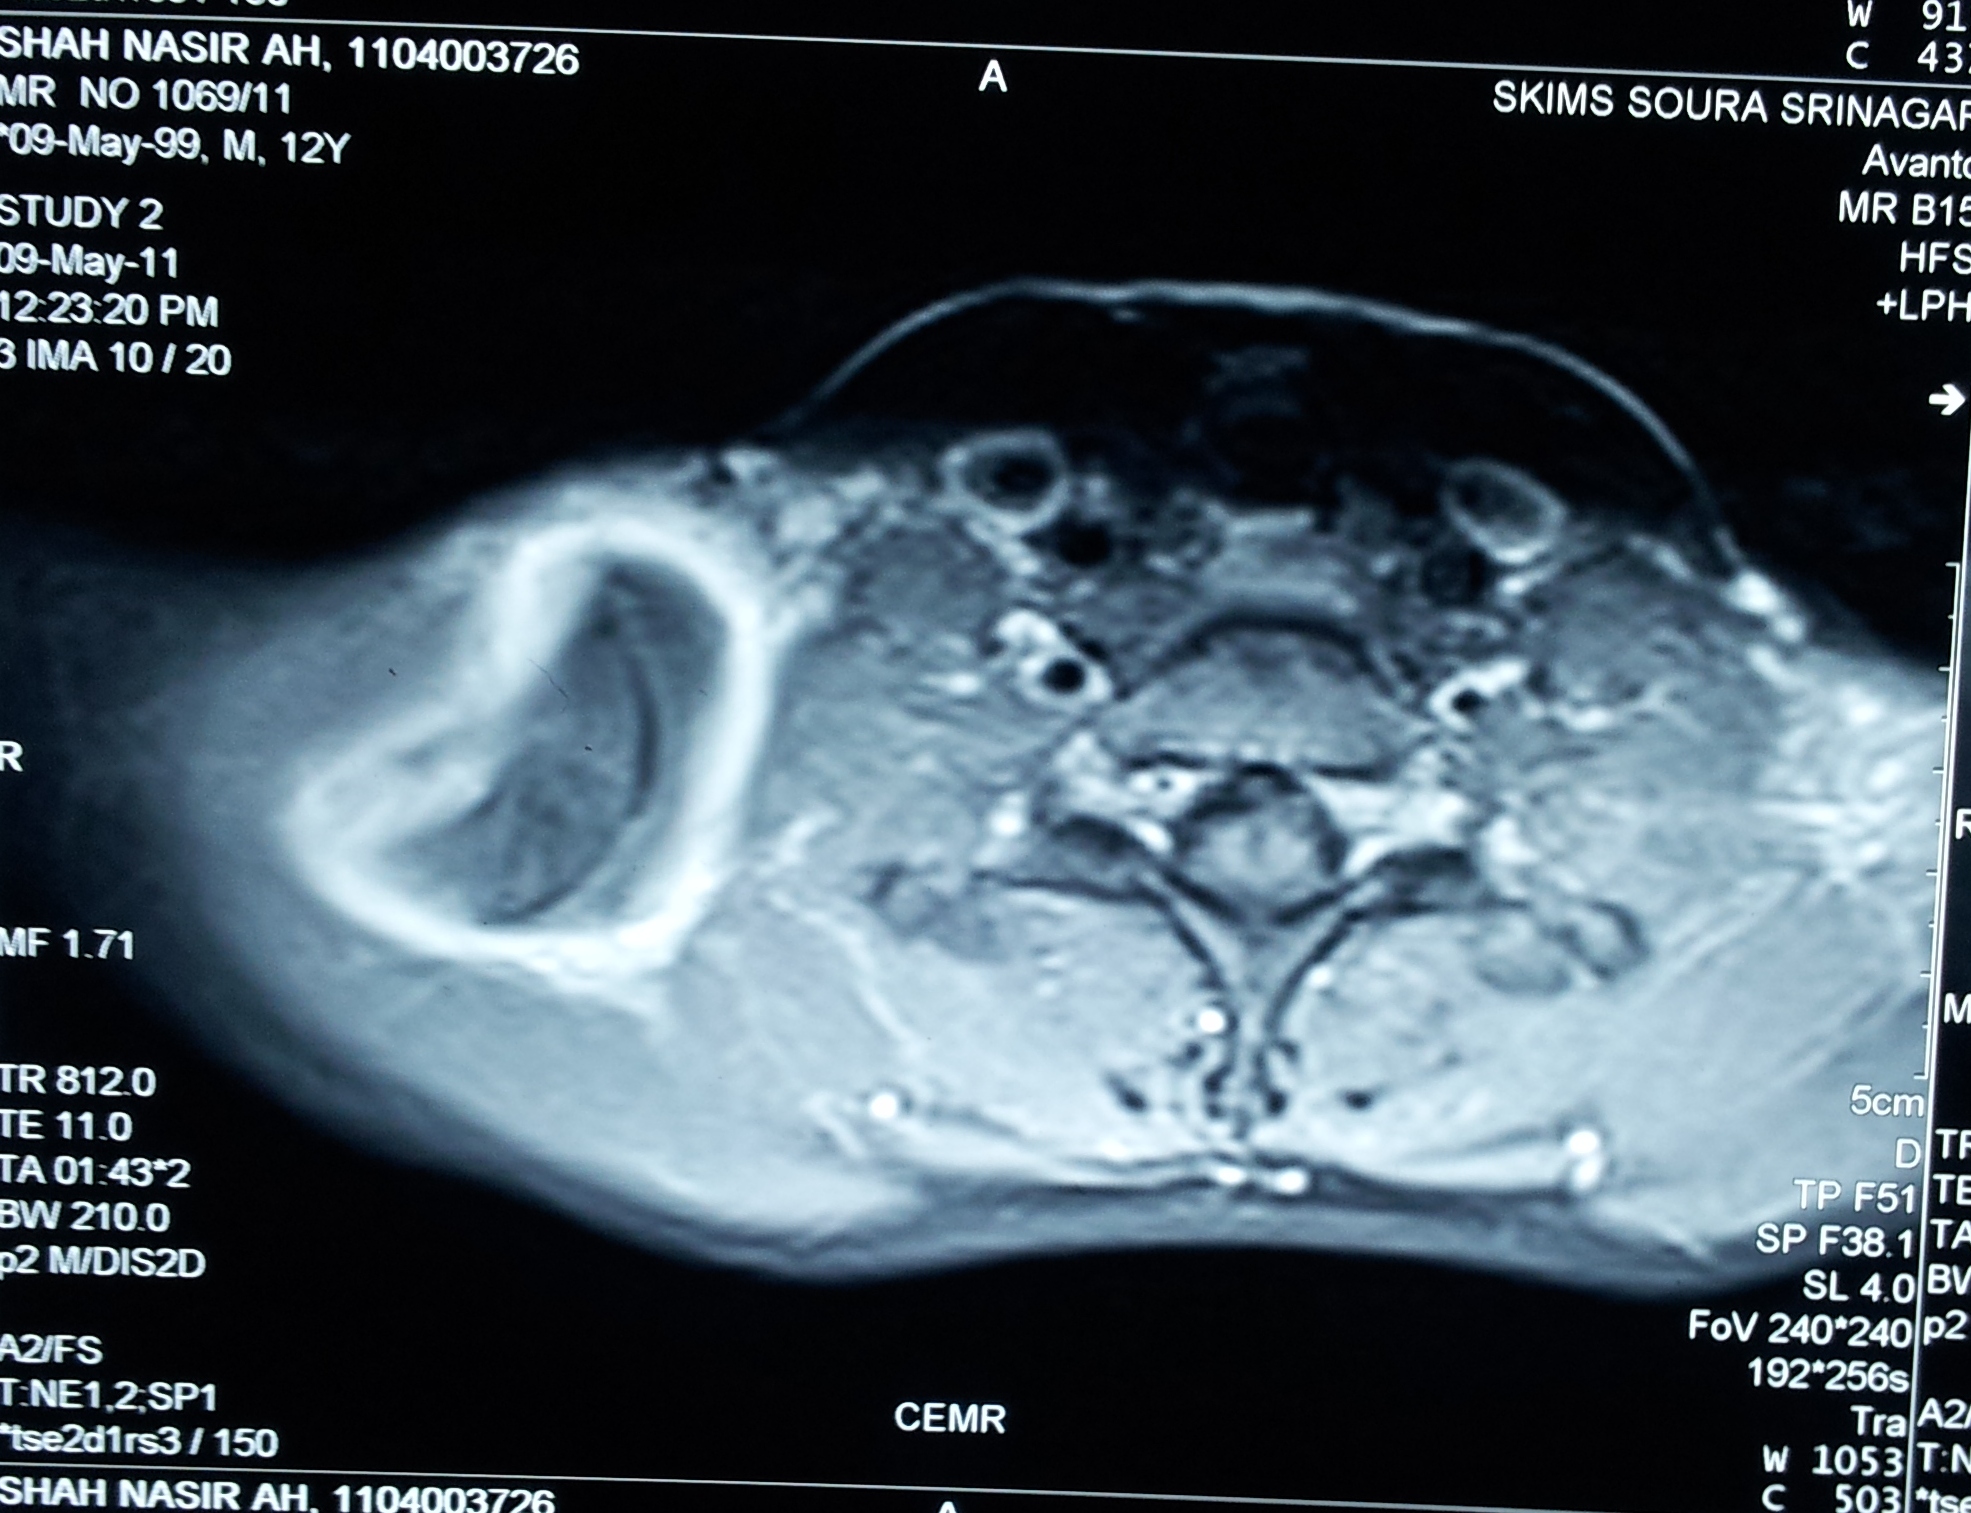

A case of hydatid cyst involving posterior triangle of neck in a 10 year old male child is reported. Diagnosis was confirmed by MRI. Surgical excision of the cyst was done. Hydatid cyst in posterior triangle should be considered one of the possibilities in evaluating a cystic swelling in this region.